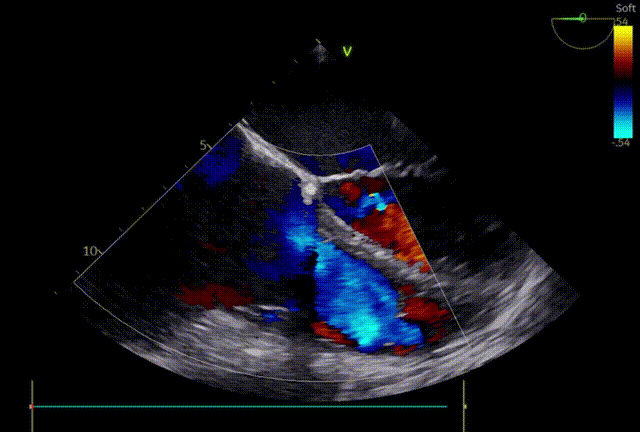

术前超声

术后超声